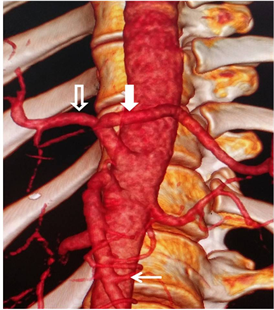

One hundred and twenty-eight patients (80%) had a classical anatomical configuration of celiac trunk, while thirty-two (20%) had at least one AV. Two AVs were found in 15 patients (9.4%) while five other patients (3.1%) had more than two AVs. Bifurcation of celiac trunk was the most common type of AV with a total of 14 patients, including hepato-splenic bifurcation (Figure 2), with 12 patients (7.5%). The second type of bifurcation found was gastro-splenic with 1.3% (Figure 3). Collateral arteries were the second most frequent type of AVs with a

Figure 2. Enhanced abdominal CT-scan showing on 3D reconstruction, a hepato-splenic bifurcation with a common hepatic artery (hollow arrow), a splenic artery (full arrow) and a stomachic coronary artery of inferior mesenteric artery origin (thin arrow).